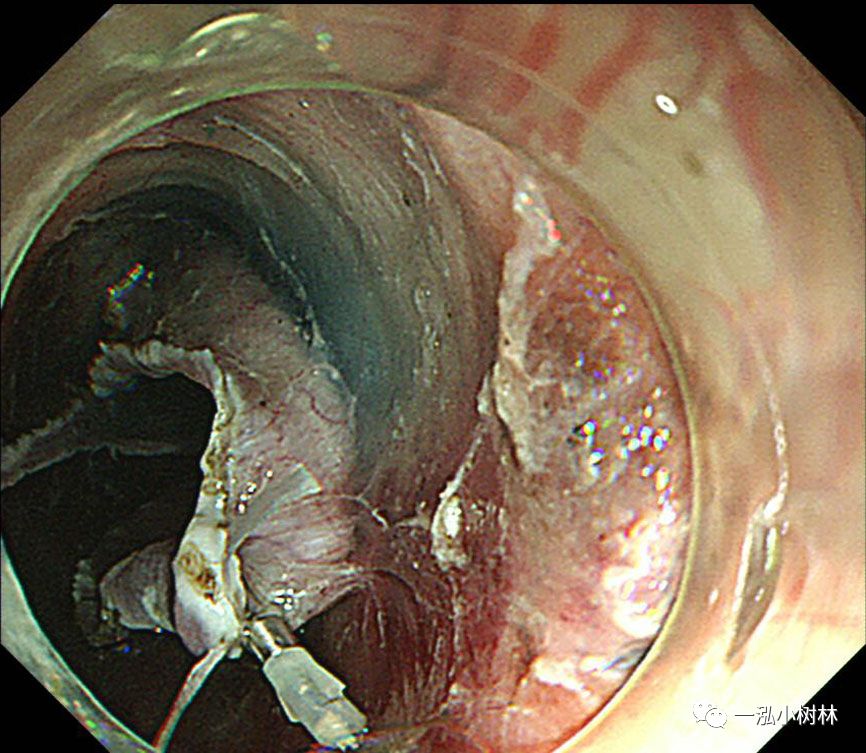

图9 在标本的背面进行钛夹牙线牵引

图10 牵引线从嘴中拉出以产生牵引力